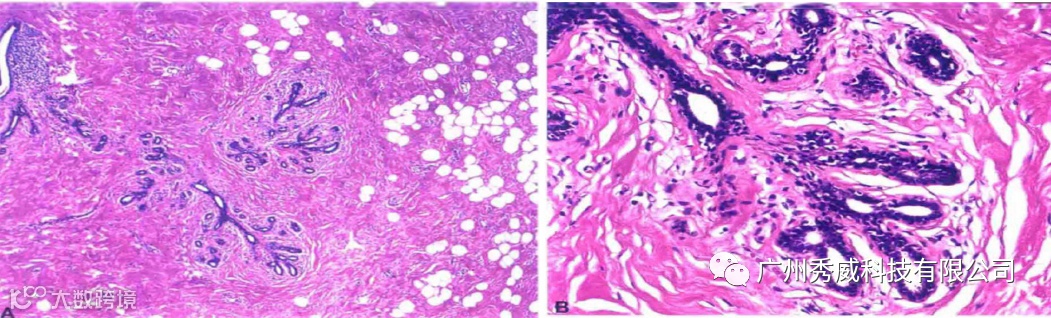

光镜病变:①正常乳腺小叶;②小叶间纤维组织常增生;③部分导管可增生或扩张; ④可伴发肿、纤维腺瘤、乳头状瘤和乳腺癌等。